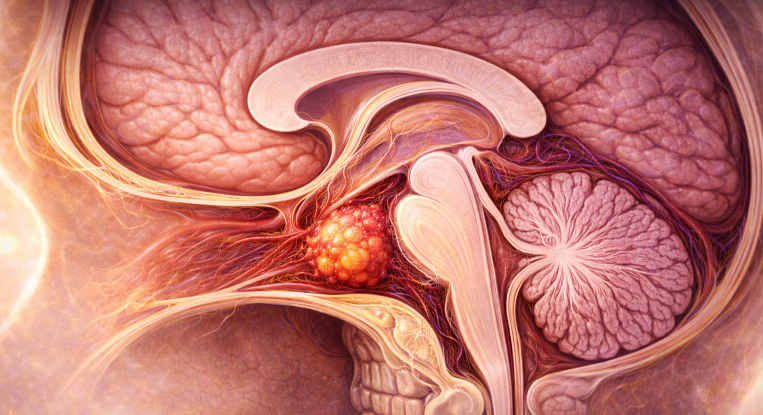

Adenoamele hipofizare sunt tumori benigne (non-canceroase) care se dezvoltă din celulele glandei hipofize, o structură endocrină esențială situată la baza creierului, în șaua turcească a osului sfenoid. Hipofiza reglează secreția majorității hormonilor din corp, influențând activitatea tiroidei, glandelor suprarenale, ovarelor/testiculelor, precum și creșterea și lactația.

- Macroadenoamele hipofizare apar ca mase tumorale cu priza de contrast localizate la nivelul șeii turcești, eventual cu extensie superioară (supraselară) spre nervii optici sau, mai rar, inferioară, în sinusul sfenoid; de multe ori ele se pot extinde și lateral, în sinusurile cavernoase (structuri vasculare venoase formate în grosimea meningelui care mărginește lateral șaua turcească, prin care trec arterele carotide interne).